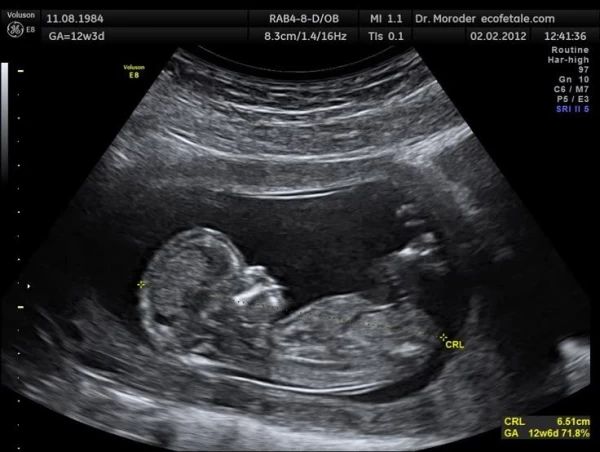

۳. کاربردهای گسترده امواج اولتراسونیک 🌀کاربرد در مهندسی و صنعت 💥 آزمون های غیرمخرب (NDT): از امواج اولترا سونیک برای شناسایی عیوب داخلی مواد، اندازه گیری ضخامت و تعیین خواص الاستیک مواد استفاده میشود. تکنیک هایی مانند "امواج لمب" برای بازرسی صفحات و پوسته ها کاربرد دارند . 💥 پلیسه گیری الکتروشیمیایی: مطالعات تجربی نشان داده که اعمال امواج اولترا سونیک بر فرآیند پلیسه گیری الکتروشیمیایی، میتواند نرخ براده برداری را در جریان های مشخص، از ۲۰ تا ۱۰۰ درصد افزایش دهد. همچنین این امواج منجر به افزایش کارایی جریان الکتریکی در دماهای مختلف میشوند . 💥 تمیزکاری اولترا سونیک: یکی از شناخته شده ترین کاربردهاست که در آن قطعه در مایع غوطه ور شده و امواج پرتوان، آلودگی ها را از سطح آن جدا میکنند . 💥 جوشکاری و پردازش مواد: از امواج اولترا سونیک برای جوشکاری مواد غیرهم جنس، برش دادن و بهبود فرآیندهای مکانیکی استفاده میشود . 🌀 کاربرد در پزشکی 💥 سونوگرافی تشخیصی: مهم ترین کاربرد اولترا سونیک در پزشکی است که برای تصویربرداری از بافت ها و اعضای داخلی بدن به کار میرود. از جمله محدودیت های این روش، عدم عبور امواج از استخوان و گاز است . 💥 کاربردهای نوین در جراحی: فناوری فراصوت توان بالا، کاربردهای جدیدی در جراحی های پزشکی پیدا کرده است که امکان برش و همزمان انعقاد خون را فراهم میکند . 💥 فیزیوتراپی: از امواج اولترا سونیک کم شدت برای درمان های فیزیوتراپی و تسریع بهبودی بافت ها استفاده میشود. 🌀کاربرد در غذا سازی اولتراسونیک به عنوان یک فرآیند غیرحرارتی سازگار با محیط زیست، انقلابی در صنایع غذایی ایجاد کرده است. کاربردهای آن شامل: 💥 تخریب سلولی و استخراج مواد داخل سلولی مانند استخراج روغن از دانه کنجد . 💥 غیرفعال کردن آنزیم ها و میکروب ها (پاستوریزاسیون). *💥 عمل آوری گوشت (نرم کردن گوشت). 💥 خشک کردن مواد غذایی (مانند تولید چیپس سیب). 💥 همگن سازی، امولسیون سازی و کف زدایی . 🌀 کاربرد در مهندسی شیمی و محیط زیست 💥سونوشیمی: استفاده از امواج اولترا سوند برای تغییر و بهبود واکنش های شیمیایی است. این فناوری پتانسیل زیادی برای سرعت بخشیدن به فرآیند های شیمیایی و کاربردهای صنعتی گسترده در آینده دارد . 💥 پالایش محیط زیست: از امواج اولترا سونیک برای حذف آلاینده ها از آب و خاک استفاده میشود. برای مثال، مطالعات نشان داده که این امواج میتوانند در حذف نیترات از محلول های آبی مؤثر باشند و راندمان فرآیند جذب توسط جاذب های مختلف مانند "بیوچار" را افزایش دهند . همچنین از این فناوری در کاهش حجم لجن تصفیه خانه های فاضلاب استفاده شده است . 💥 پالایش نفت: از اولترا سونیک در فرآیندهایی مانند گوگرد زدایی از نفت خام و کاهش خاصیت اسیدیته گازوئیل بهره گیری میشود .